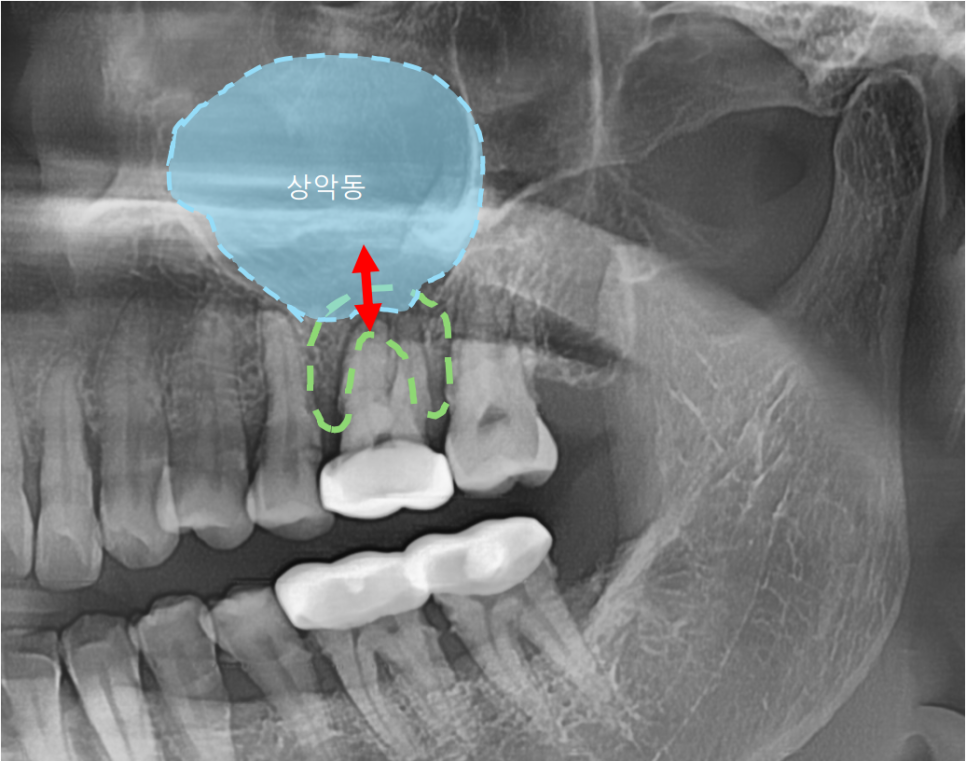

치근단 엑스레이와 CT를 확인해본 결과

통증의 원인이 되는 큰어금니 하나는

뿌리쪽에서 뿌리 끝 염증이 생긴것을 확인했습니다.

이 뿌리 끝 염증이 커질수록 잇몸이 붓고

심하게는 뼈를 녹이게 되므로

주변 치아까지 영향을 미치게 됩니다.

뿌리에 생긴 낭이 뼈를 녹여

상악뼈 양이 얼마 남지 않은

모습을 확인할 수 있습니다.

상악동이라는 코 옆의 공기주머니는

아주 얇은 막으로 둘러싸여 있어서

혹시라도 찢어지거나 뚫리게 된다면

축농증이 생길 수 있어서 조심해야 합니다.

환자분께서 비염이 있다고하셨는데

뿌리끝에 생긴 낭 때문에

불편감이 더 크셨을 수도 있습니다.